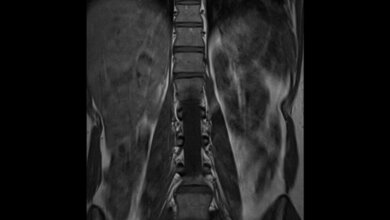

Wichtige Funktionen der Nieren

Die Nieren reinigen und filtern unser Blut. Pro Tag säubern sie rund 300 Mal die etwa sechs Liter Blut im Körper: Wichtige Substanzen wie Eiweiße oder Mineralien bleiben im Blut, Stoffwechselabfallprodukte hingegen filtert das Organ heraus und scheidet sie über den Urin aus. Aus circa 180 Litern, die täglich aus dem Blut gefiltert werden, gelangen nur zwei bis drei Liter konzentriert in die Harnblase - der Rest bleibt dem Körper erhalten. Die Nierenfunktion nimmt bei Erwachsenen kontinuierlich mit dem Alter ab. Ist sie nachhaltig eingeschränkt, kann es zu vielfältigen Beschwerden kommen. Dazu gehören Schwellungen der Beine oder des Gesichts, Müdigkeit, Übelkeit, Gewichtsverlust oder Muskelkrämpfe bis hin zum Nierenversagen im Endstadium. Chronische Nierenkrankheiten gehören zu den am stärksten ansteigenden Todesursachen in den vergangenen zehn Jahren. (idw, red)